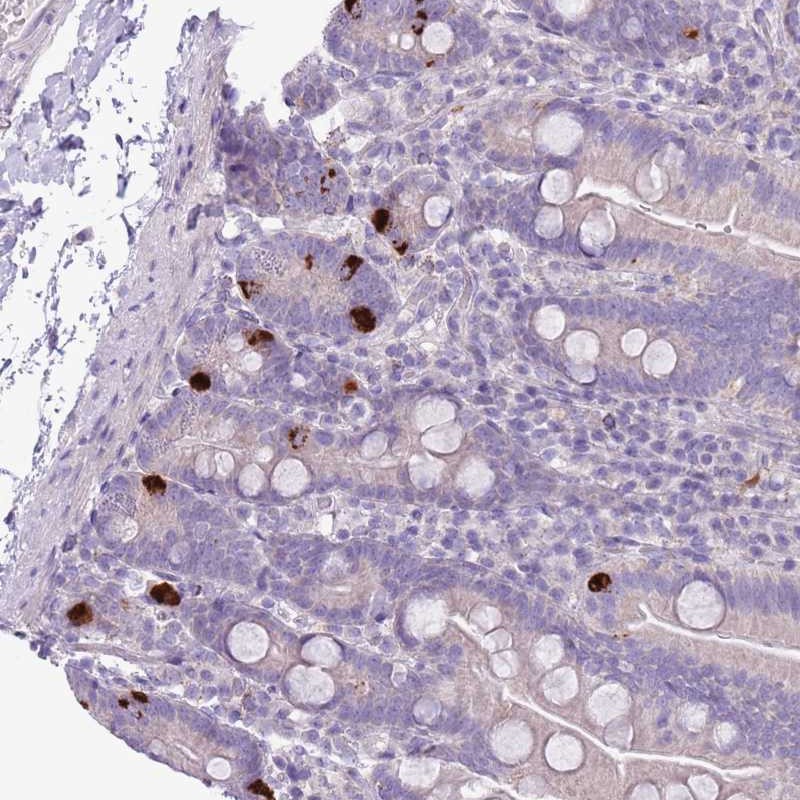

Immunohistochemical staining of human small intestine shows strong cytoplasmic positivity in enteroendocrine cells.